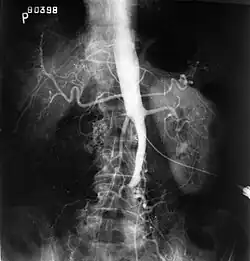

| Plate from Gray's Anatomy showing the abdominal aorta and the common iliac arteries | |

Angiography provides important information regarding the perfusion and patency of distal arteries (e.g. femoral artery). The presence of collateral arteries in the pelvic and groin area is important in maintaining crucial blood flow and lower limb viability. However, angiography should only be used if symptoms warrant surgical intervention.[2]